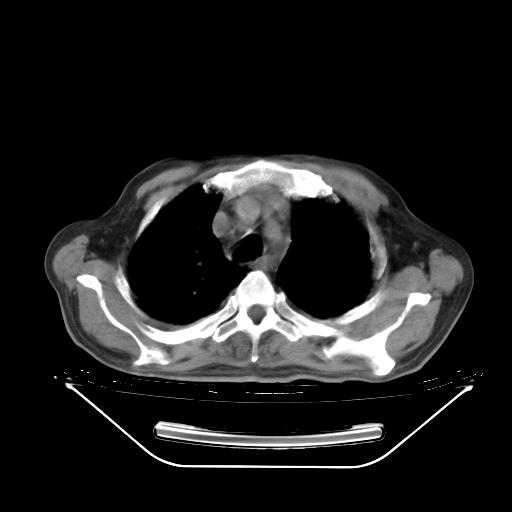

今天复查肺部CT,发现双肺广泛磨玻璃样改变。所以我把3月19日和5月9日相隔50天的肺部CT上传。请大家会诊。

5月9日肺部CT(在4月27日齐鲁医院肺部CT描述部分肺组织磨玻璃样改变,12天后肺组织广泛磨玻璃样改变)

2009年5月9日肺部CT

大致读了系列胸部CT:纵隔窗无明显异常,肺窗:从4、27至今:主要是双肺中下野外带可见毛玻璃样改变,目前处于急性肺泡炎阶段,至于原因考虑1、结替组织或胶原血管性疾病所致?2、恶性疾病如恶组在肺部所致的表现或细支气管肺泡癌?3、药物或其它原因如肺蛋白沉着症所致肺泡炎目前不太可能?总之,明天就去请我院的呼吸科、感染科、血液科和临免专家会诊哈。